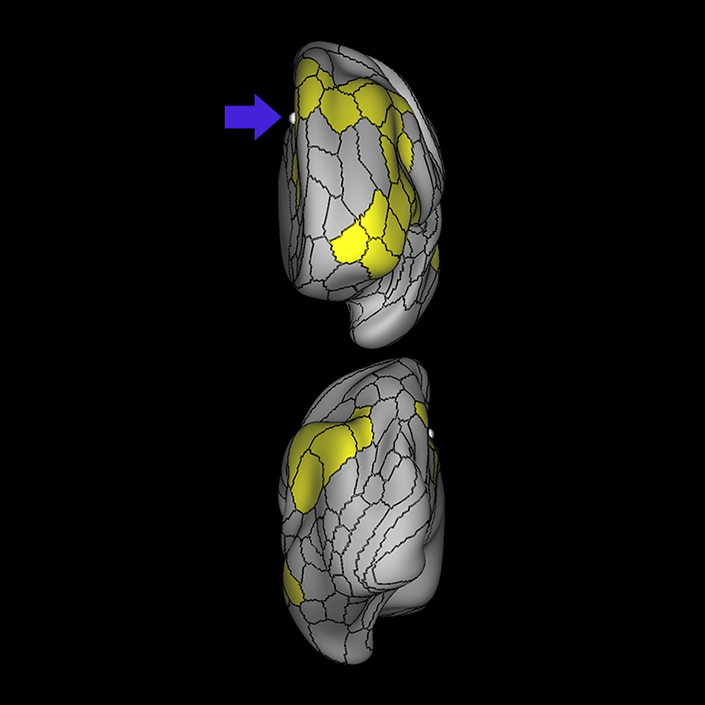

ᐅ SummaryArea 44: part of the inferior frontal gyrus of the lateral frontal lobe. Translates abstract and intentional information in the prefrontal cortex to more detailed representations to help guide the production of verbal and manual actions. In addition to its known association with Broca's area, is sometimes represented as part of Broca's complex ᐅ Where is it?Area 44 is at the posterior most part of the inferior frontal gyrus. It is the anterior bank of pars opercularis of the IFG. ᐅ What are its borders?Area 44 borders area 45 anteriorly and area 6r posteriorly. Area 8C is its medial border and its inferior border is wedged between then upper borders of Areas 6R and 6V. Its superior edge borders IFSp and IFJa. Its opercular surface is FOP4. ᐅ What are its functional connections?Area 44 demonstrates functional connectivity to areas SFL, IFSp, IFJa, 45, 47s, 47L, 9a, 9m, 8AV, 8BL and 8C in the dorsolateral frontal lobe, area 8BM in the medial frontal lobe, area 55b in the premotor areas, areas FOP5, AVI and PSL in the insula- opercular region, areas TGd, STSdp and STSvp in the temporal lobe, areas PFm, and PGi in the inferior parietal lobe, and no areas in the medial parietal lobe. ᐅ What are its white matter connections?Area 44 is structurally connected to the arcuate/SLF and the FAT. Connections with the arcuate/SLF project posteriorly and wrap around the Sylvian fissure to the middle temporal gyrus to end at TE1a and TE1m. There are also projections from the arcuate/SLF before it terminates to parcellations A5 and STSdp. The majority of the inferior connections of the frontal aslant tract end at 44, the tract is connected superiorly to superior frontal gyrus parcellations SFL, 6ma and s6-8. Local short association bundles are connected with 45 and 8C. White matter tracts from 44 in the right hemisphere have less consistent connections with the arcuate/SLF. ᐅ What is known about its function?Area 44 translates abstract and intentional information in the prefrontal cortex to more detailed representations to help guide the production of verbal and manual actions. Area 44, in addition to its known association with Broca's area, is sometimes represented as part of "Broca's complex", including Brodmann Areas 45, 46, 47 and the mesial supplementary motor area of 6, which contribute to a frontal-subcortical circuit. The right pars opercularis has also been implicated in cognitive inhibition in the overall context of working memory. |

A: lateral-medial

B: anterior-posterior

C: superior-inferior

DTI image |